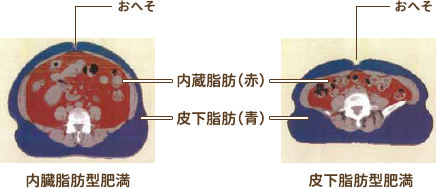

⑲内臓脂肪CT

CTで体脂肪面積を測定し、内臓脂肪型肥満を見分けるのに役立ちます。体脂肪は内臓脂肪と皮下脂肪に分類されますが、内臓脂肪の過剰な蓄積は、血糖・中性脂肪・血圧の上昇など様々な形で血管を傷つけ、動脈硬化を引き起こす原因となります。